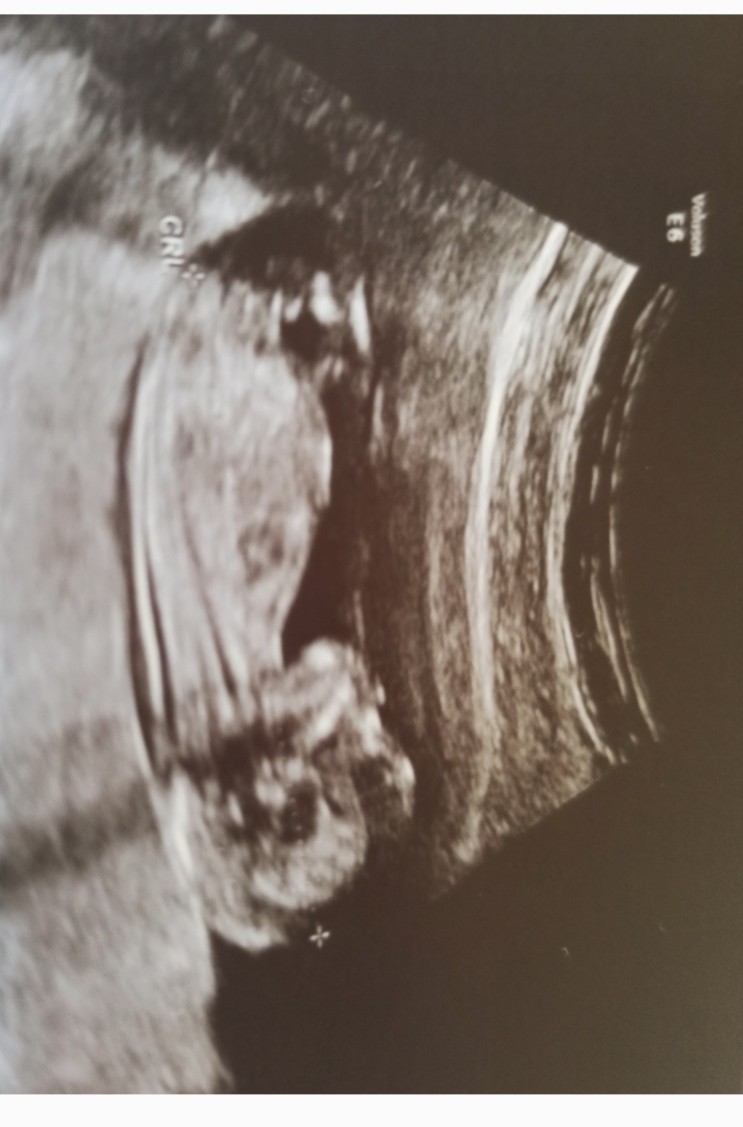

Z pierwszych mam takie. Fajne badanie, ruszają nóżkami i rączkami. Lekarz sprawdzi czy mają dobra budowę serca, czy są wszytskie narządy wewnętrzne czy jest ryzyko wad wrodzonych.

• Screenshot_2022-07-11-12-00-00-092_com.miui.gallery.jpg

Screenshot_2022-07-11-12-00-00-092_com.miui.gallery.jpg

154,2 KB · Wyświetleń: 106